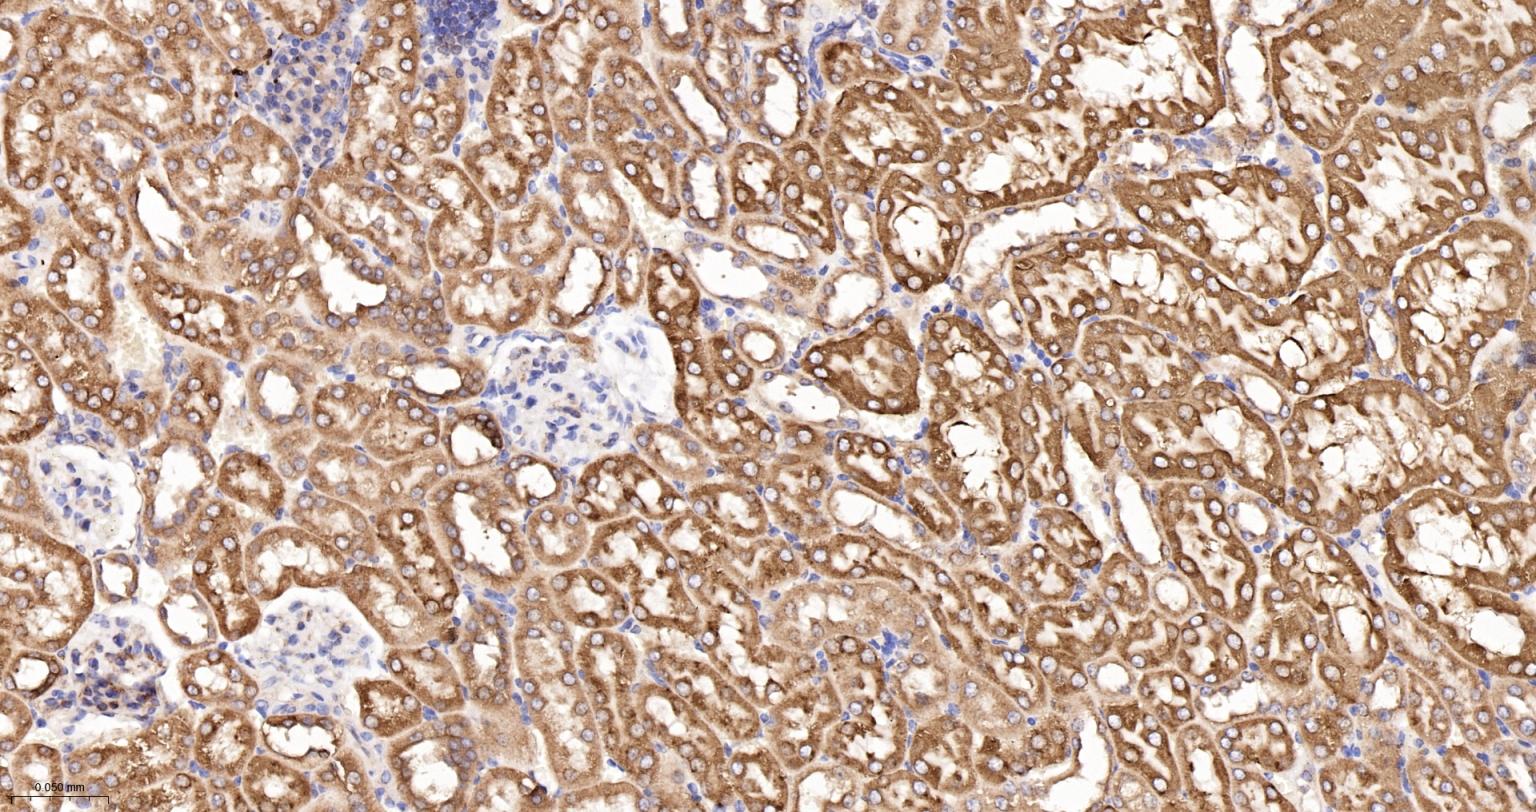

Paraformaldehyde-fixed, paraffin embedded Mouse Kidney; Antigen retrieval by boiling in sodium citrate buffer (pH6.0) for 15 min; The section was incubated with CYPOR Monoclonal Antibody, Unconjugated (bsm-61747R) at 1:200 overnight at 4°C, followed by conjugation to the bs-0295G-HRP and DAB (C-0010) staining.